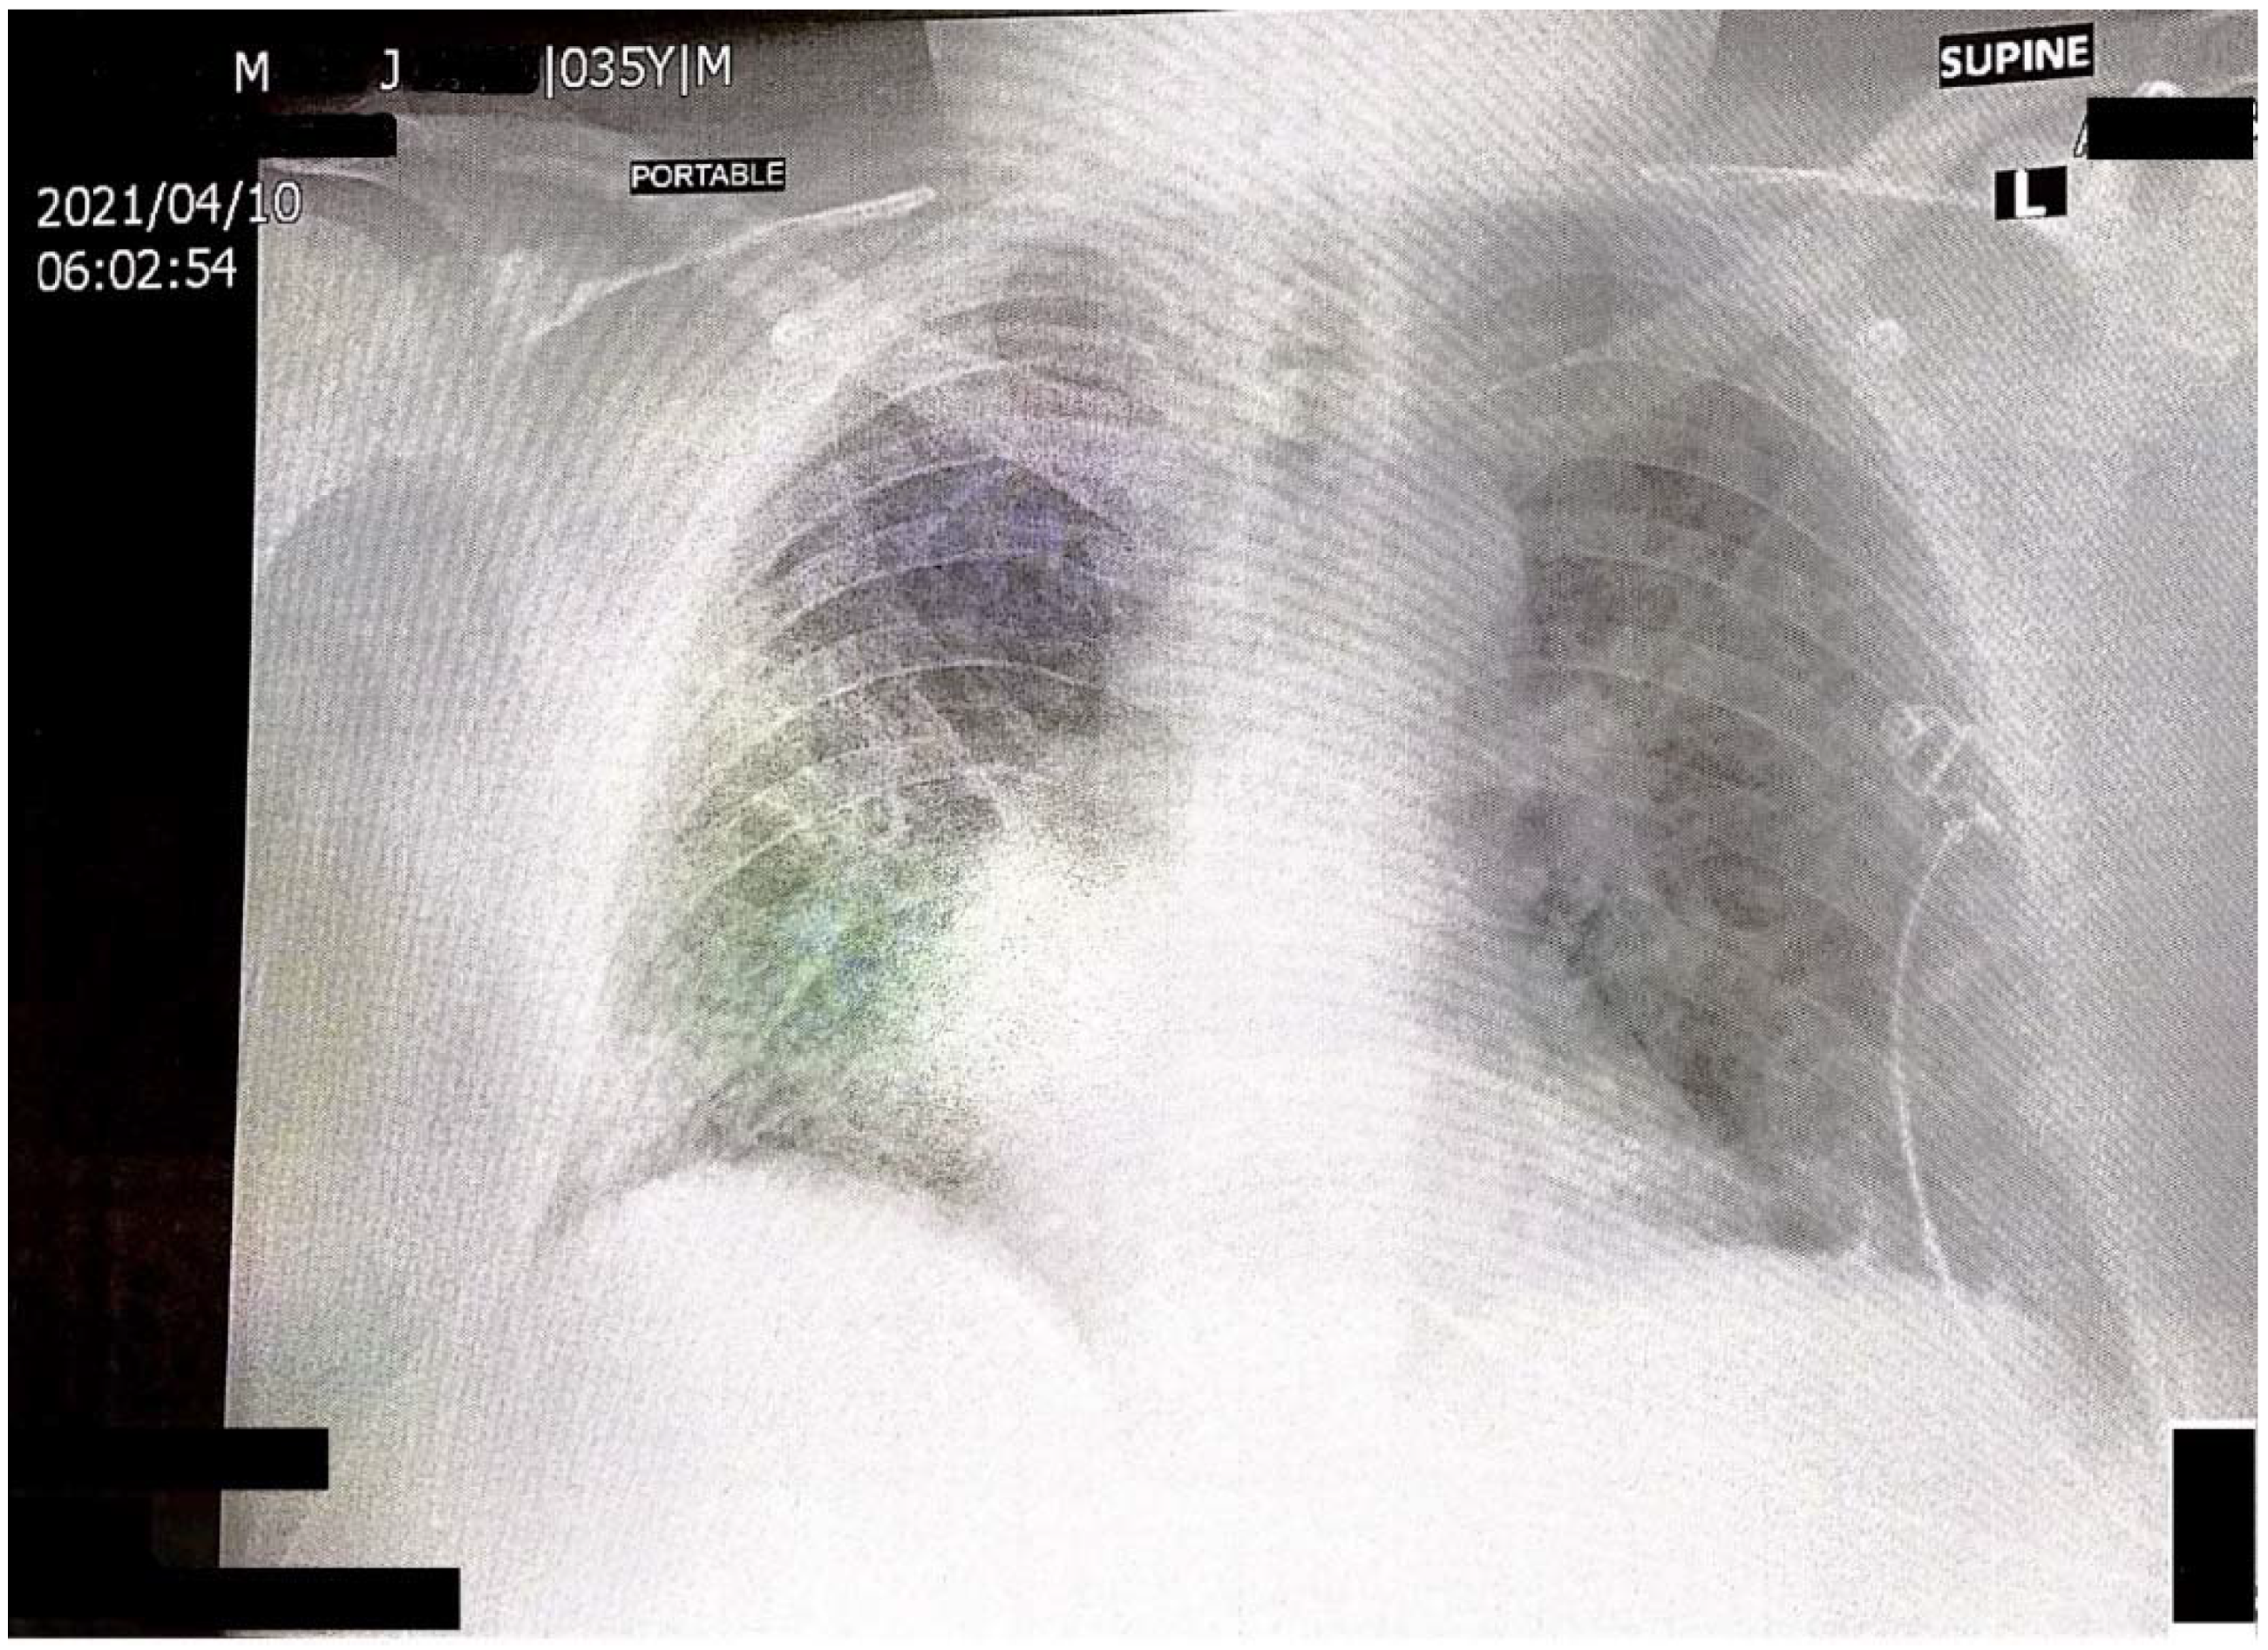

Spontaneous Post-COVID-19 Pneumothorax in a Patient with No Prior Respiratory Tract Pathology: A Case Report

2. Case Report